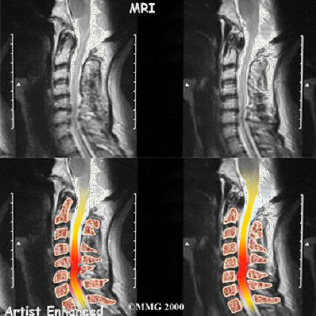

Por lo general, en estos casos es necesario recurrir a un especialista en cirugía de columna que puede diagnosticar la hernia de disco a partir de sus antecedentes de síntomas y un examen físico. Su médico preguntará acerca del dolor y el entumecimiento que podrían ser causados por la irritación de uno o más de los nervios de la columna cervical. El especialista le solicitará exámenes de diagnóstico como una resonancia magnética de columna cervical, siendo este último el examen de elección.